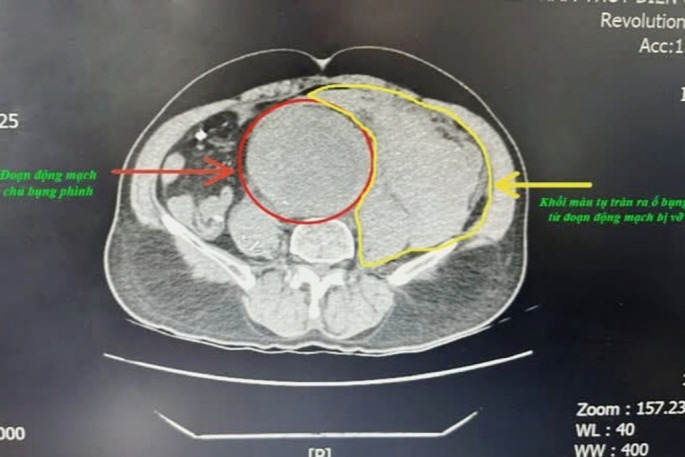

Tại bệnh viện, bệnh nhân đau bụng dữ dội, da xanh nhợt, mạch không bắt được và huyết áp không thể đo được. Kết quả chụp CT Scanner cho thấy bệnh nhân bị phình động mạch chủ ngực đoạn dưới thận lan đến động mạch chậu hai bên, trong đó khối phình đã vỡ và gây tụ máu sau phúc mạc với số lượng lớn.

Trong quá trình phẫu thuật, các bác sĩ đã nhanh chóng kẹp động mạch chủ bụng trên và dưới túi phình để ngăn chặn tình trạng chảy máu tiếp tục vào ổ bụng. Kíp phẫu thuật ghi nhận ổ bụng của bệnh nhân chứa khoảng 2.000ml máu loãng lẫn máu cục, cùng với một vết rách lớn ở động mạch chủ vỡ vào sau phúc mạc. Bệnh nhân được thay thế đoạn động mạch chủ bụng bị phình bằng một đoạn động mạch nhân tạo.